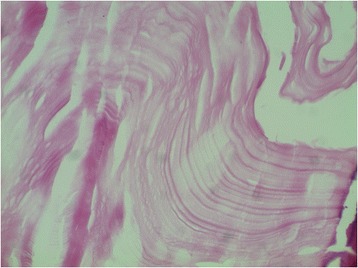

Figure 7.

Histological appearance of the abdominopelvic cysts. The stain shows an eosinophilic and lamellar membrane corresponding to cuticular membrane of hydatid cysts (hematoxylin and eosin stain; original magnification, ×200).